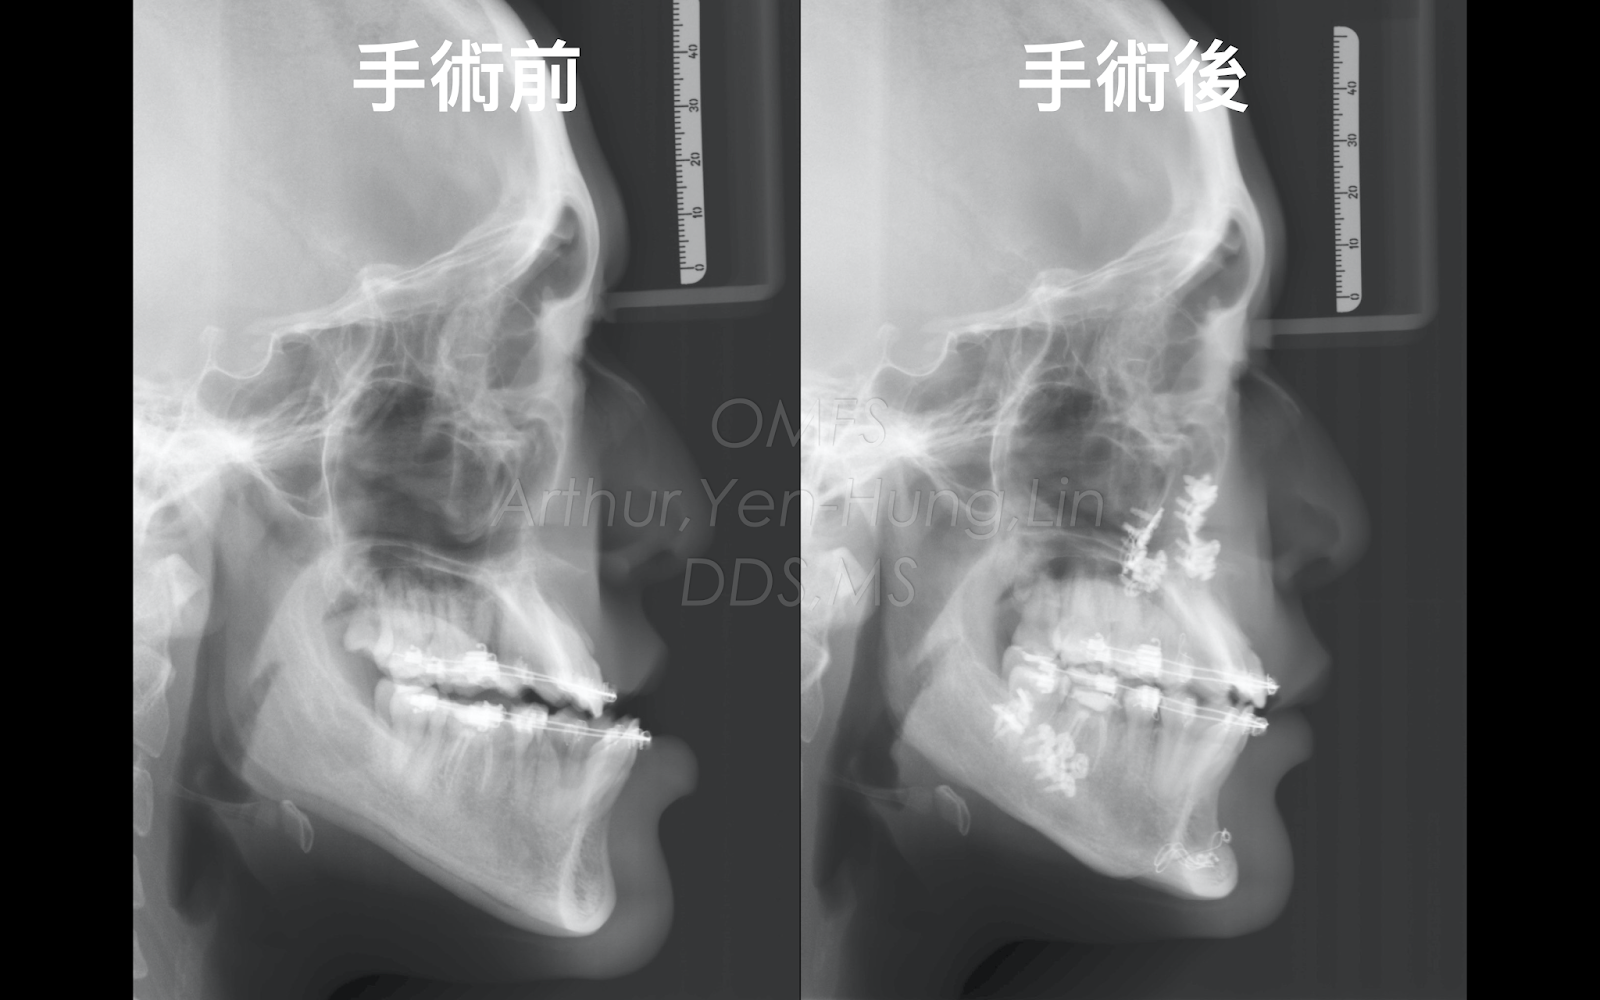

顳顎關節盤移位(TMJ Disc Displacement)對顏面歪斜(Facial Asymmetry)之影響

病患多年以來,右側顳顎關節常常疼痛不舒服, 張口時會覺得卡卡的,且 有 喀喀聲(C licking Sound ),最近覺得 下巴歪斜且咬合不正,想接受正顎手術的評估。 經過進一步檢查後 發現,病患張口運動時,下顎會偏向患側(右側),安排核磁共振 ( Magnetic Resonance Imaging , MR I)影像檢查,顯示右側顳顎關節盤為不可復位性前移位(Anterior Disc Displacement without Reducction, ADDwoR)。這樣的長期右側顳顎關節不穩定,是造成病患長期關節疼痛與張口問題的主要原因,因此建議病患接受右側顳顎關節盤復位手術(Disc Reposition)來改善顳顎關節穩定性。 經過顳顎關節手術治療與咬合板配戴半年,核磁共振影像追蹤檢查顯示右側顳顎關節盤位置明顯改善,下顎門牙中線中線對齊,下巴回正, 張口時卡卡的與 喀喀聲都消失了 。 病患這才終於明白,原來當初下巴歪斜與咬合不正的問題,竟然跟顳顎關節有這麼大的關係。 顳顎關節盤復位手術,使下顎骨往下往前逆時鐘旋轉( Counterclockwise Rotation , CCWR ),造成術後下顎前牙(淺綠色)明顯往前,呼吸道變寬(藍色雙箭頭),下巴略為往前的效果。 手術後可見顏面中線(黃色)與下顎中線(淺綠色)吻合。 手術前右側顳顎關節盤(淺綠色)為不可復位性前移位( ADDwoR ), 手術後顳顎關節盤(淺藍色)恢復為正常位置。 手術後下巴中線對齊,下顏面歪斜改善。 手術後下排門牙中線對齊。